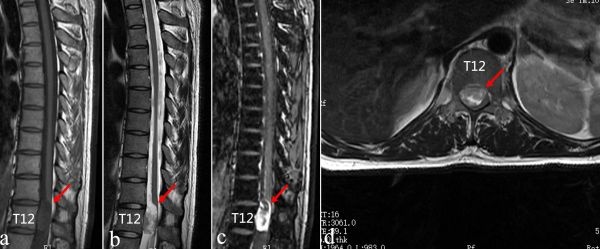

“这不是腹部疾病,高度怀疑是椎管内肿瘤。”李亚明为他进行详细的体格检查,排除了腹部疾病后,判断可能是脊椎相关疾病导致的脊髓神经损害,进而引起腹部疼痛。随后检查结果提示:胸11-12节段椎管内有一巨大的髓外硬膜内肿瘤,占据超90%的椎管容积,脊髓已明显受压偏向一侧。

根据神经系统体表定位,胸10-12节段的脊髓皮支控制脐平面与耻骨联合平面之间的区域,李亚明判断该节段脊髓神经受肿瘤压迫引起的根性疼痛,才是患者腹痛的“元凶”。椎管内肿瘤的常见类型为神经鞘瘤、脊膜瘤及神经纤维瘤,结合患者病史和影像学病理学等各项检查,患者椎管内的肿瘤为神经鞘瘤的可能性更大。

肿瘤影像图。